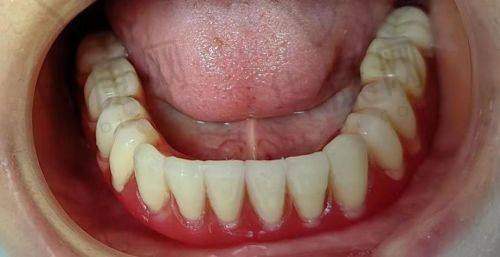

湖南湘西口腔医院何春秀全口即刻种植牙之诊疗成效

经过一段时间的修复,我的全口即刻种植牙成效非常显著。现在我可以像正常人一样吃饭、说话了,再也不用担心牙齿缺失带来的尴尬和不便。牙齿变得整齐美观,让我的笑容也更加自信了。而且,种植的牙齿稳定性特别强,咀嚼功能也修复得良好,我可以尽情享受美食了。这种改变真的让我非常惊喜,也非常感激何春秀医生和湖南湘西口腔医院的医护人员。